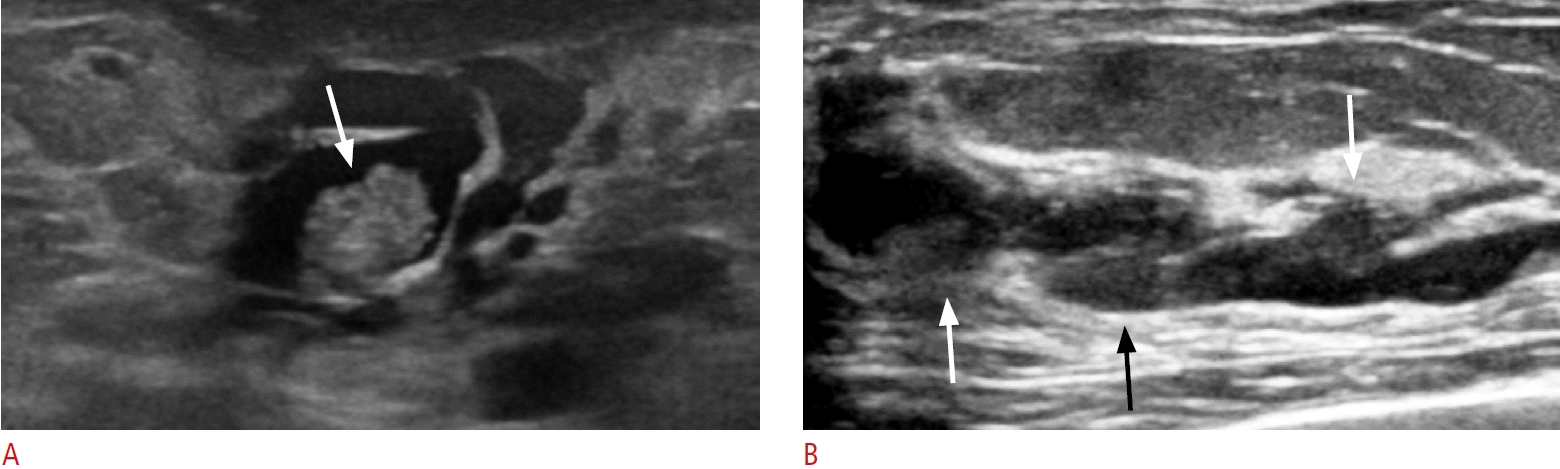

17. Ban K, Tsunoda H, Watanabe T, Kaoku S, Yamaguchi T, Ueno E, et al. Characteristics of ultrasonographic images of ductal carcinoma in situ with abnormalities of the ducts. J Med Ultrason (2001). 2020; 147:107–115.

18. Watanabe T, Yamaguchi T, Tsunoda H, Kaoku S, Tohno E, Yasuda H, et al. Ultrasound image classification of ductal carcinoma in situ (DCIS) of the breast: analysis of 705 DCIS lesions. Ultrasound Med Biol. 2017; 43:918–925.

7. Kim WH, Chang JM, Moon WK, Cho N, Yi A, Koo HR, et al. Intraductal mass on breast ultrasound: final outcomes and predictors of malignancy. AJR Am J Roentgenol. 2013; 200:932–937.